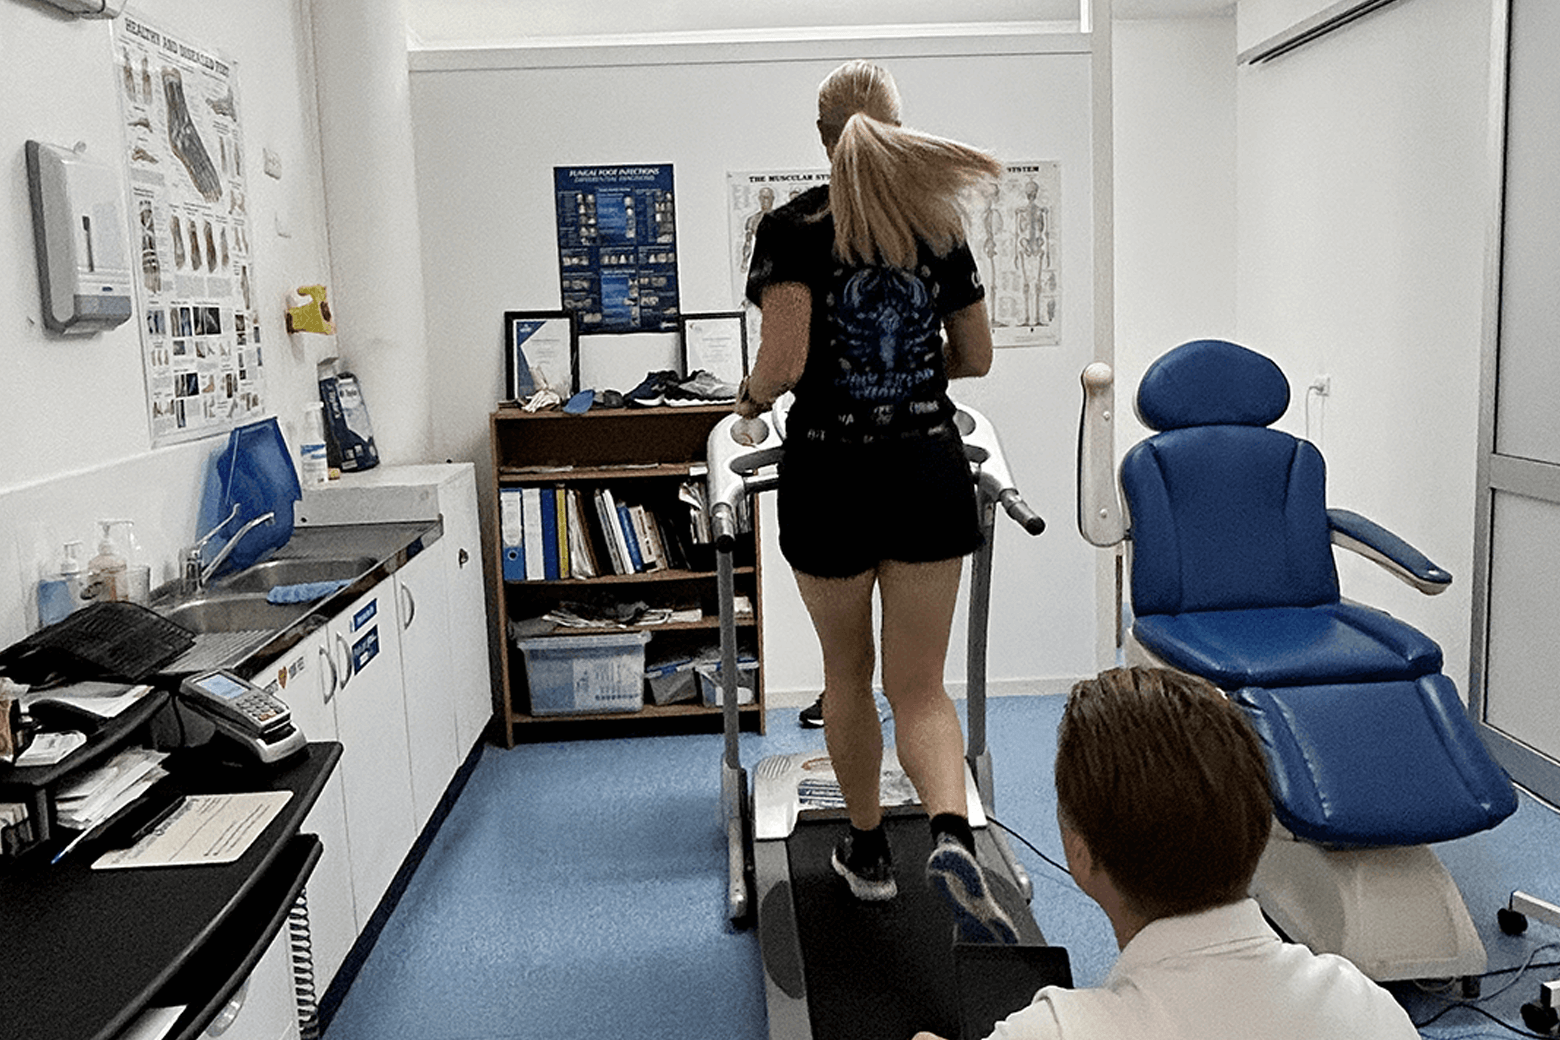

Gait Analysis

At Chris Garside Podiatry, we take a holistic approach to gait analysis, delving beyond your feet to gain profound insights into your body’s movement patterns.